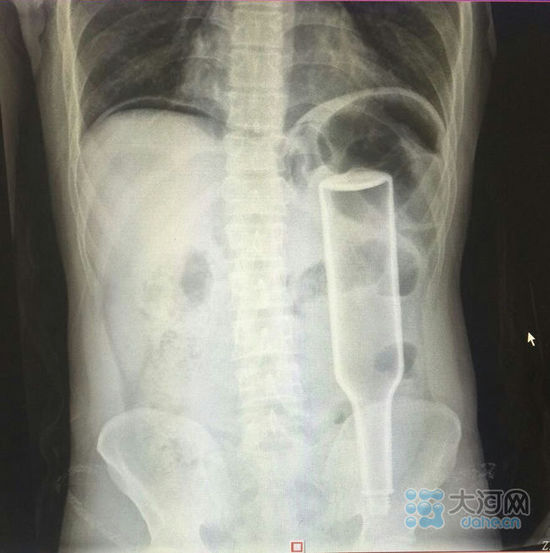

看這片子,花露水瓶子已經(jīng)很“深入”了。

大河網(wǎng)訊在鄭州務(wù)工的外地男子王某,下班到家后閑著沒事兒干,于是將一個長18厘米的花露水瓶子塞進(jìn)了自己的肛門,不過因?yàn)橛昧^猛,快感沒來,瓶子卻把直腸給戳破了,疼得受不了了,王某羞答答地來到鄭州人民醫(yī)院就診,醫(yī)生給他做了手術(shù),現(xiàn)在已經(jīng)出院。